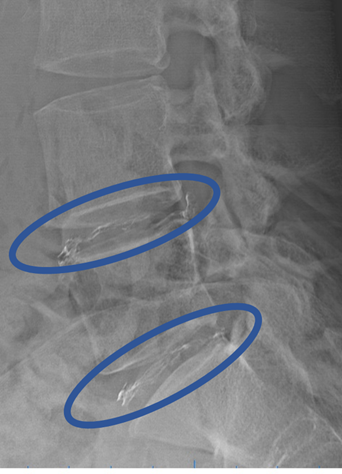

DiscoGelを入れた後の画像になります。

治療は 30分 程度で終了

回復室で休憩後、歩いて帰院されました。